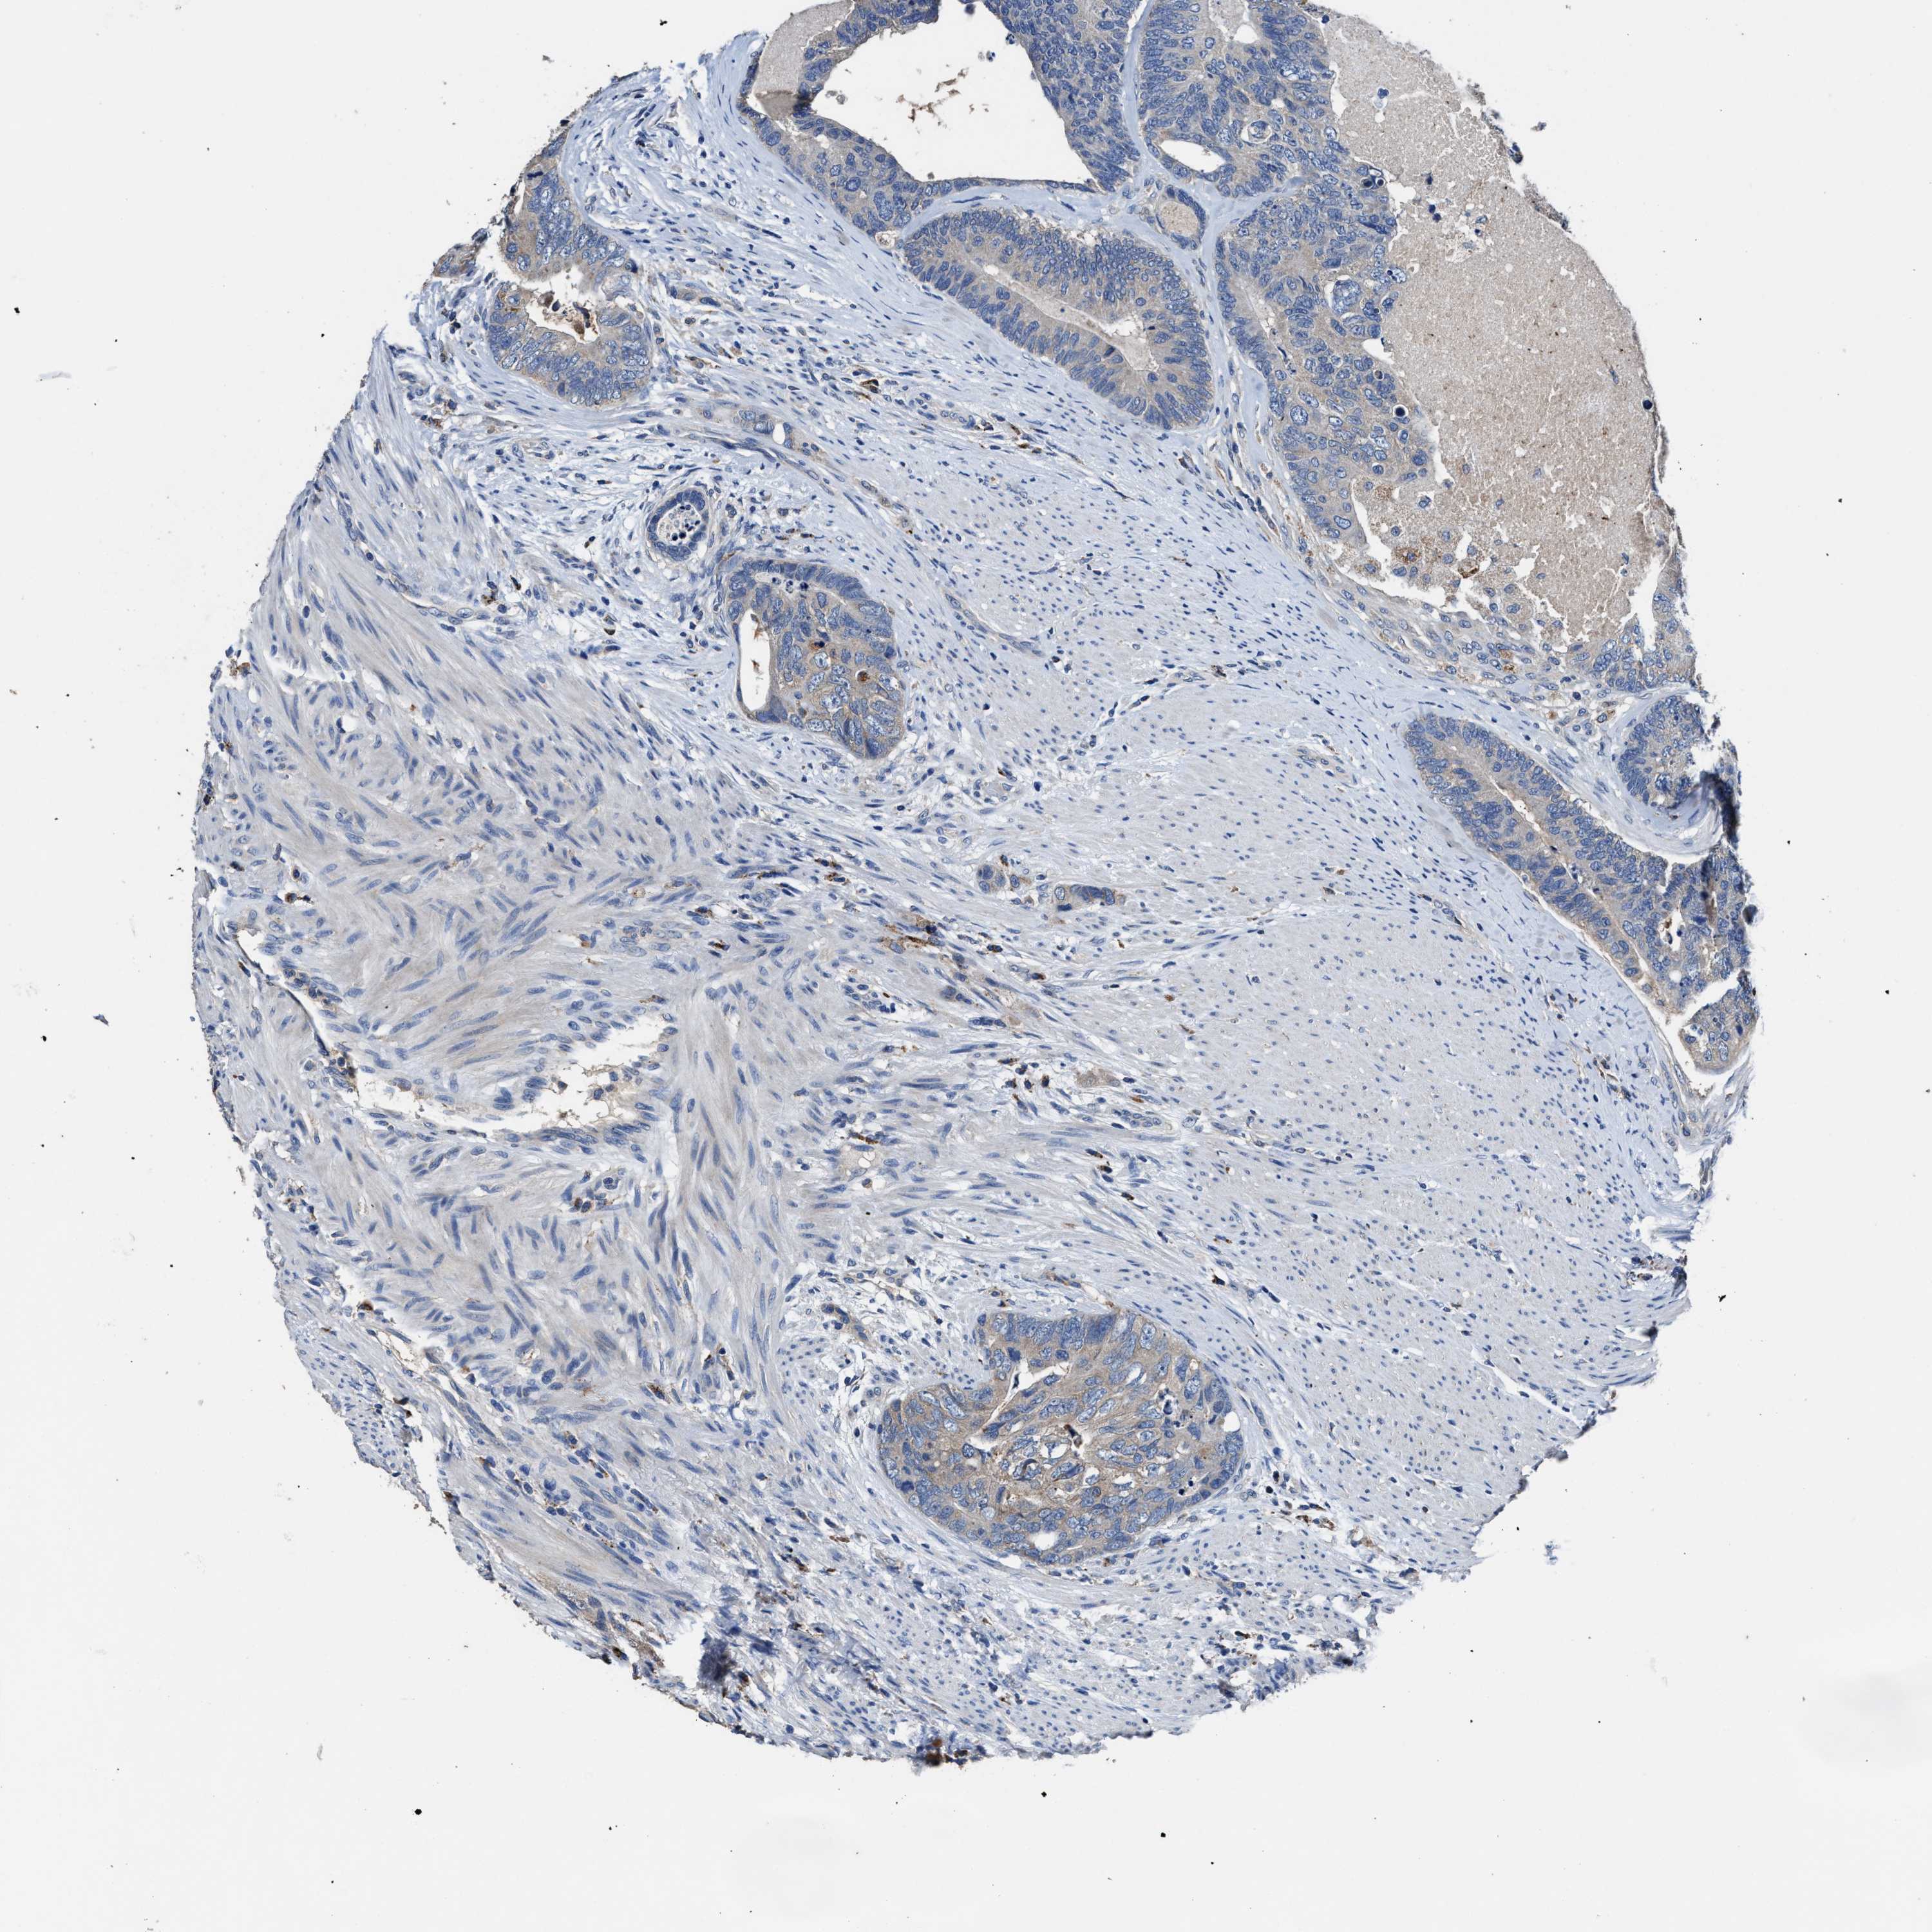

CANCER COLORECTAL CANCER Show tissue menu

ANTIBODIES

AND

VALIDATION